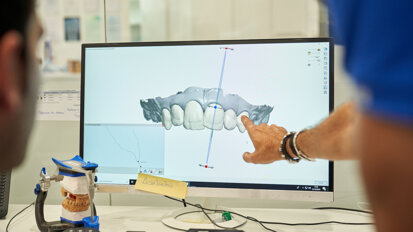

Obecnie bezwzględnie wymagana jest diagnostyka tomograficzna przed każdym takim zabiegiem. Jednocześnie pożądaną jest ścisła współpraca i konsultacje z laryngologami, chociażby do oceny stanu błony śluzowej nosa i drożności anatomicznych ujść z zatok szczękowych do nosa. Przypomnijmy, że ich drożność ma kluczowe znaczenie dla powodzenia zabiegu i zminimalizowania prawdopodobieństwa zakażeń bakteriami beztlenowymi.

Anatomiczna klasyfikacja została stworzona na podstawie analizy 200 obrazów tomografii wolumetrycznej u pacjentów z całkowitym bezzębiem lub z brakami skrzydłowymi. Każde z tych badań (CBCT) obejmowało 2 zatoki szczękowe: lewą i prawą. Jest to klasyfikacja ułatwiająca podjęcie decyzji, która z metod podnoszenia zatoki szczękowej będzie dla pacjenta odpowiednia i czyli pomaga w doborze metody do przypadku.

Klasyfikację oparto na obrazie z tomografii, jaki uzyskuje się w przekrojach czołowych (wieńcowych) lub prostopadłych do krzywej panoramicznej ułożonej równolegle do łuku zębowego górnego. Klasa „zero” (Tab. 1) została wyróżniona jako sytuacja kliniczna, w której brak bezwzględnych wskazań do zabiegu podniesienia dna zatoki szczękowej z 2 powodów: